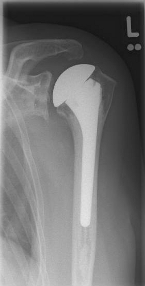

Short stem prostheses as modern implants for omarthrosis and acetabular wear

left: X-ray image of a short-shaft prosthesis